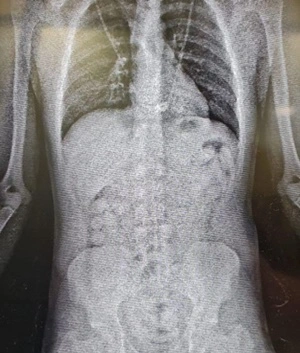

Dois homens e uma mulher foram presos no Aeroporto de Fortaleza pela Polícia Federal, na operação “Falcão Peregrino” — em combate ao tráfico internacional de drogas. As capturas foram realizadas em ações entre os dias 19 e 23 de maio. Os detidos tentavam embarcar com destino para Paris, na França. Eles transportavam 100 cápsulas de cocaína no estômago.

Foto: ReproduçãoTrês pessoas são presas com cocaína no estômago no aeroporto de Fortaleza

Os três foram autuados por tráfico internacional de drogas e permanecem à disposição da Justiça Federal.